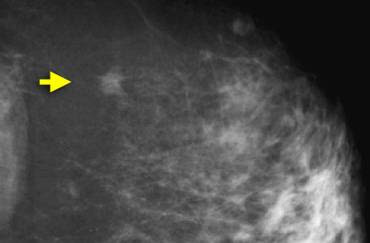

- Nódulos: qualquer opacidade com algum contorno arredondado e definido segundo a forma, os contornos e a densidade.

- Nódulos redondos ou ovóides, circunscritos (ou com 75% das margens visibilizadas), não calcificados e sólidos à ultrassonografia;

- Assimetria focal sem outra alteração.

Recomendações: controle em 6 meses (unilateral, só da mama com alteração), 12, 24 e 36 meses, bilateral.